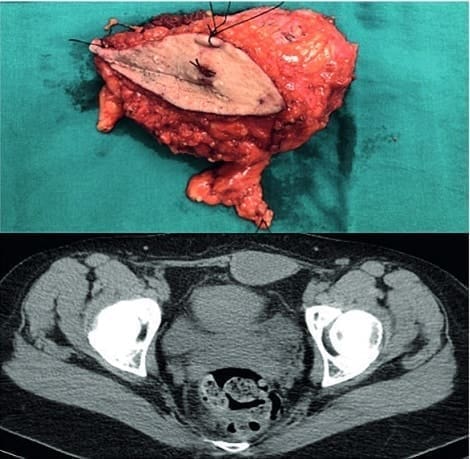

Figura 1. Caso clínico 1, femenina de 22 años, en la parte superior se observa la masa resecada,

en la parte inferior se presenta la resonancia. Fuente: Hospital Miguel Servet, Servicio de cirugía general.